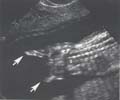

Les pieds bots sont le

plus souvent isolés mais doivent faire rechercher :

- Un problème neurologique (spina-bifida) ![]()

- Une polymalformation

- Certains nanismes

- Une anomalie osseuse de la jambe

- Une anomalie chromosomique en particulier trisomie 18

Les pieds bots bilatéraux doivent faire rechercher des anomalies positionnelles des mains (mains botes ou mains crispée) ou d’autres anomalies associées, en particulier cardiaque qui peuvent orienter vers une anomalie chromosomique.

Un pied bot unilatéral peut être associé à une agénésie tibiale.